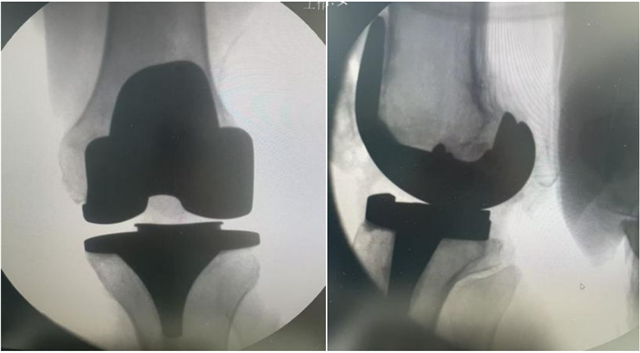

术后影像

经过充分的术前准备,在椎管内麻醉下,手术团队为患者施行了“左侧人工全膝关节置换术”。手术过程顺利,出血少,患者安返病房。在骨伤科医护团队的精心照护和康复师的指导下, 术后第二天,她已能稳稳站立,并在助行器帮助下迈出步伐。“没想到这么快就能走,感觉轻松多了!”郭阿姨和家属对治疗效果非常满意。